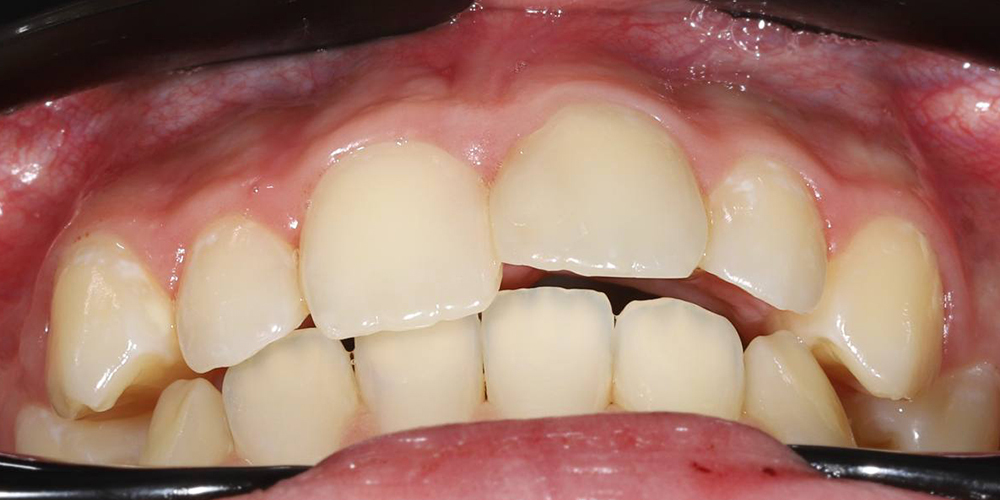

Комплексная реабилитация при скелетных и зубных нарушениях с использованием элайнеров и имплантации